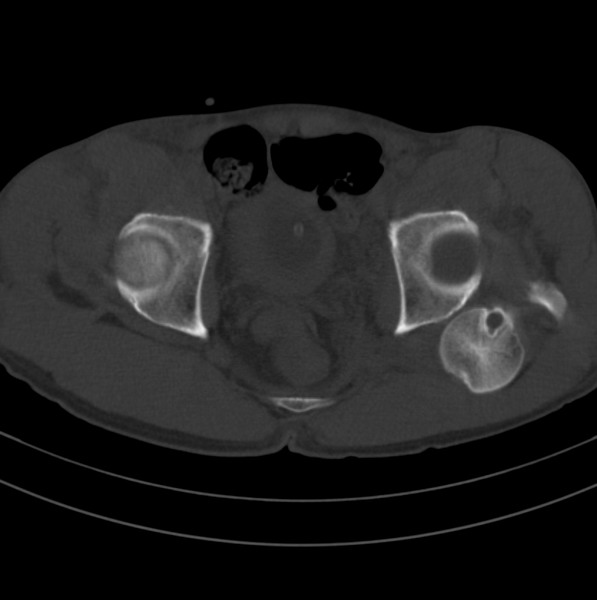

标题: CT18589:股骨头囊状阴影怎么下结论?

男、53

股骨头内的囊状阴影怎么下结论?

1.左髋后脱位。

左侧髋关节后脱位;左侧股骨头疝窝。

左侧髋关节后脱位;左侧股骨头疝窝

脱位够厉害的